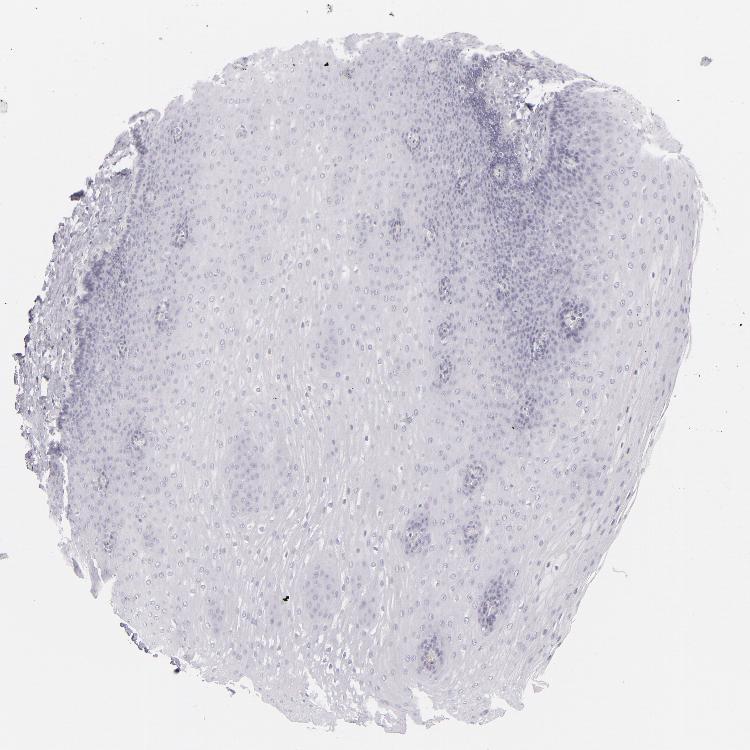

ESOPHAGUS - Antibody stainingi

Antibody staining in the annotated cell types in the current human tissue is reported as not detected, low, medium, or high, based on conventional immunohistochemistry profiling in selected tissues. This score is based on the combination of the staining intensity and fraction of stained cells.

Each image is clickable and will lead to virtual microscopy that enables deeper exploration of all samples and also displays staining intensity scores, fraction scores and subcellular localization as well as patient and tissue information for each sample.

Antibody CAB002221

Squamous epithelial cells Not detected